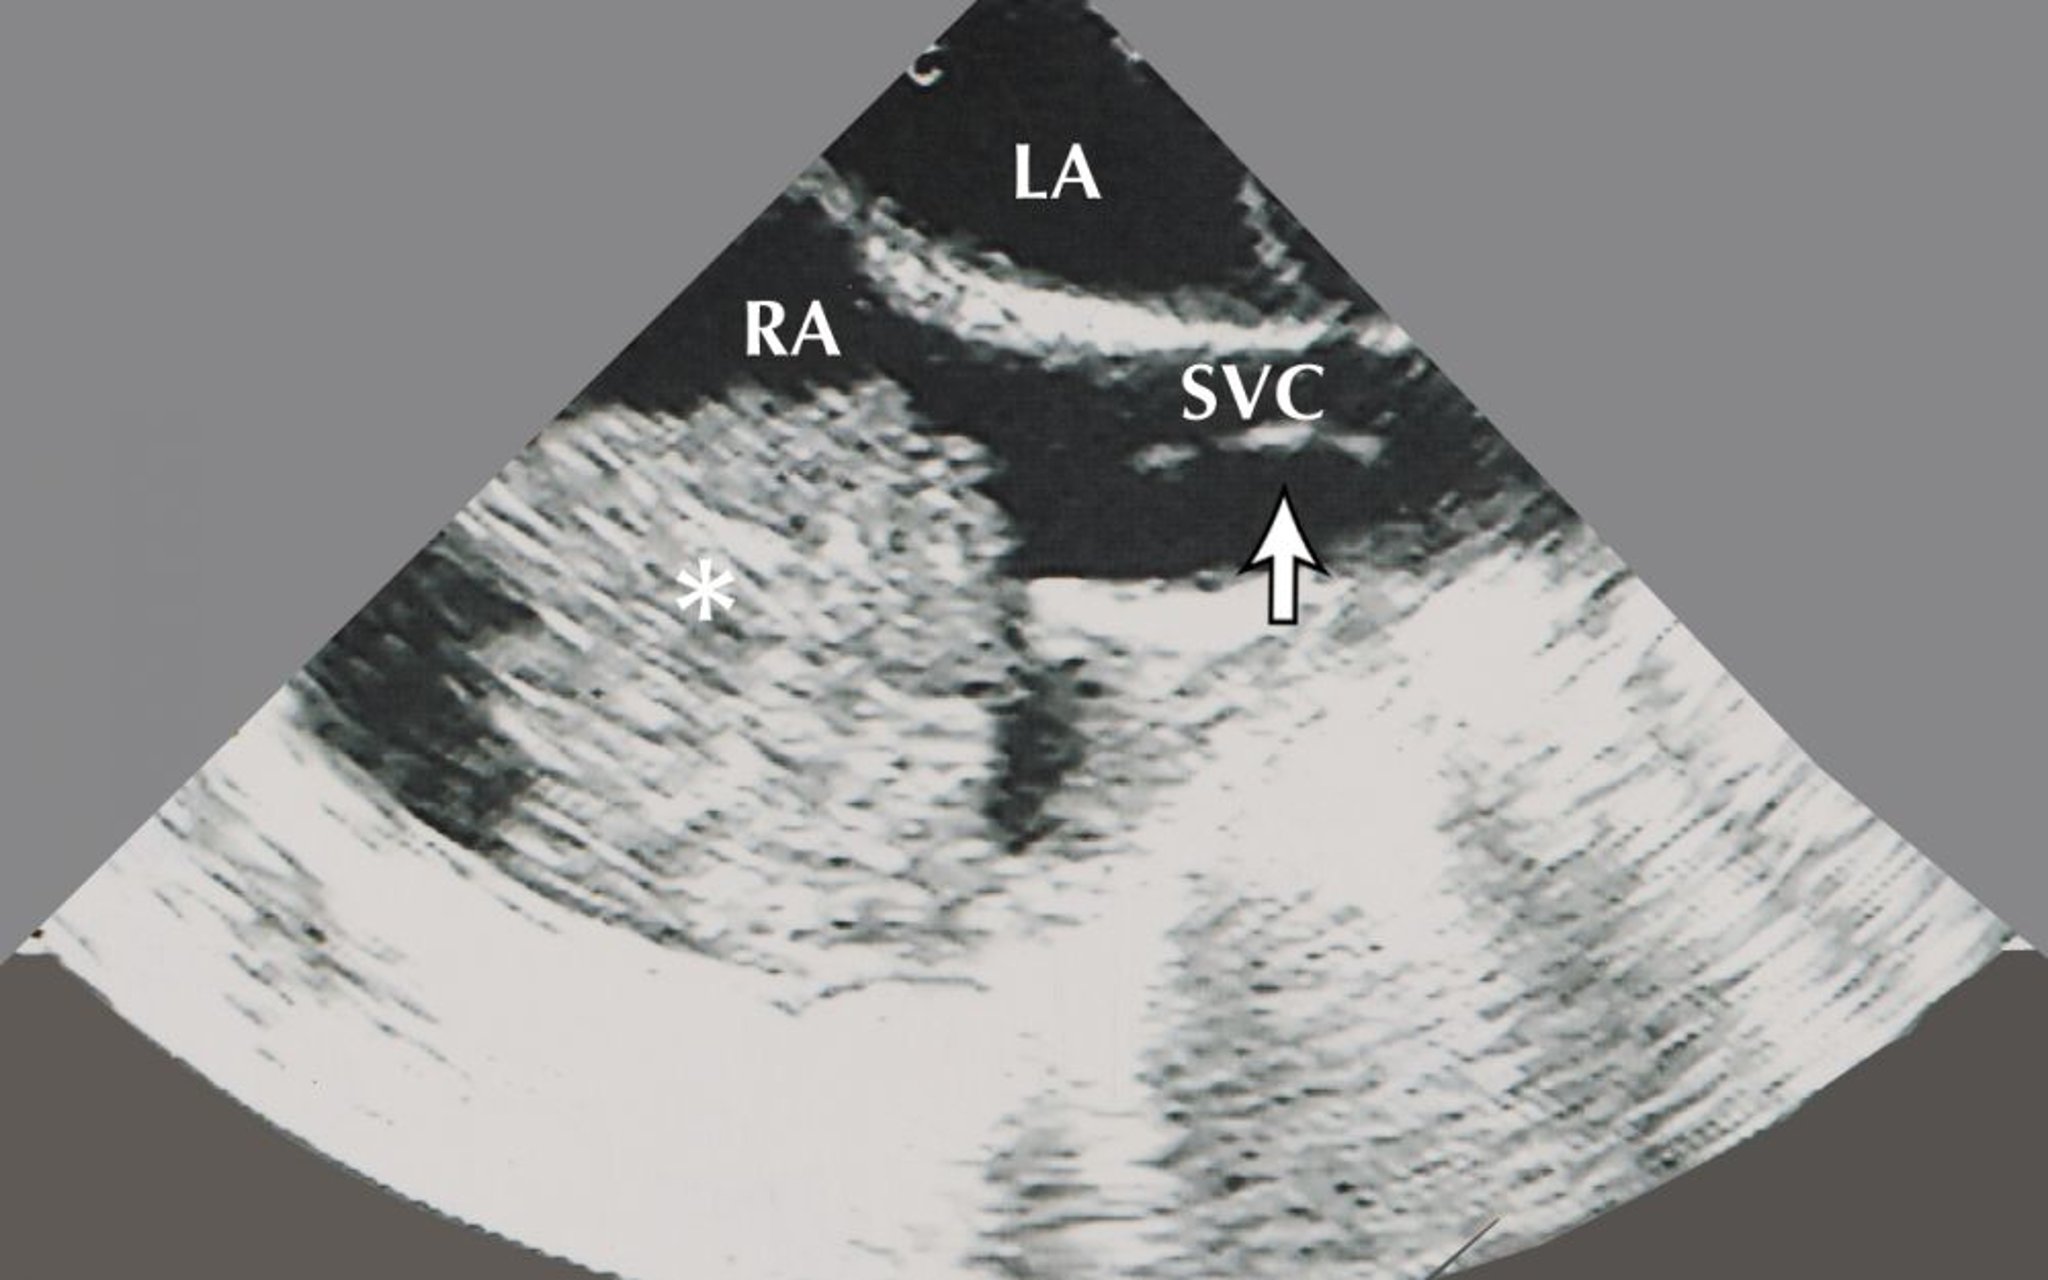

Atriales Myxom (Echokardiogramm)

Dieses Bild zeigt ein Vorhofmyxom (gekennzeichnet durch das Sternchen) im rechten Vorhof (RA). Auf diesem echokardiographischen Bild sind auch der linke Vorhof (LA) und ein Bioptom (durch den Pfeil angezeigt) in der oberen Hohlvene (SVC) zu sehen.